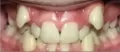

Добрый день, у меня такая проблема — клык вырос поверх других зубов и когда улыбаюсь он виден и иногда натирает губу из нутри то есть если часто говорю и смеюсь.

Хотел спросить что мне делать?! Было бы лучше избавиться от него и конечно что-то подешевле.

Добрый день. Правильное решение в вашем случае, естественно, выравнивание зубов при помощи брекет систем . Дешевым этот метод назвать сложно, но это однозначно единственное правильное решение.

Срок лечения может занять от 8 месяцев до года, при этом выровнятся и все остальные зубы, а также исправится прикус.